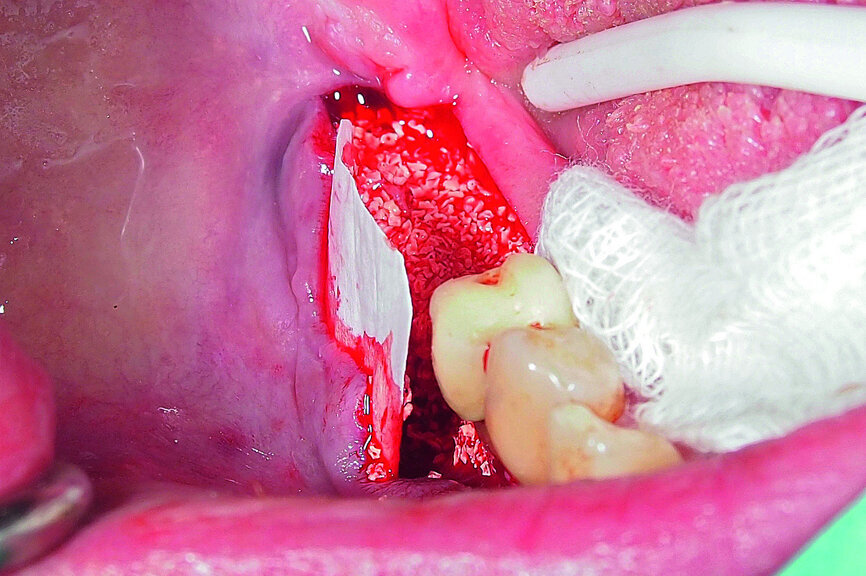

Fig. 17: Creation of space in between the buccal and lingual lamina with the intact attached periosteum on the buccal.

Fig. 19: Bone defect filled with xenograft and covered with an absorbable collagenous membrane.

A demonstration of this technique is shown in Figures 13 to 20. This case presents an elderly woman who had lost her teeth in the lateral mandible decades ago. Being a healthy non-smoker with good oral hygiene, no history of periodontal disease and low masticatory forces, she was an adequate candidate for bone grafting together with implant placement. The future restorative margins allowed the usage of ridge splitting (Figs. 13 & 14). Therefore, we opted for a ridge split with vertical releases carried out utilising a partial-thickness flap. The periosteum was left attached in order not to impede the perfusion of the buccal plate (Fig. 15). After ridge splitting, the buccal and lingual plates were separated with the use of bone spreaders (Split-Control Plus, Meisinger) to allow the placement of two GC Aadva Standard implants, one of 3.3 mm in diameter and 8.0 mm in length and the other measuring 4.0 mm in diameter and 8.0 mm in length (Figs. 16–18).